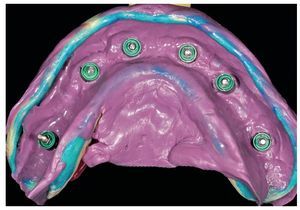

Fig. 65. Los implantes en el maxilar superior, integrados mediante técnica sin colgajo, y los pilares correspondientes para prótesis atornilladas.

Fig. 66. Los pilares provisionales se aíslan de la cavidad oral mediante dique de goma antes de unirlos a la prótesis provisional.

Fig. 76. La toma de impresión definitiva en el maxilar superior tiene lugar a la altura del hombro del implante.

Fig. 78. Vista detallada de la impresión del maxilar superior.